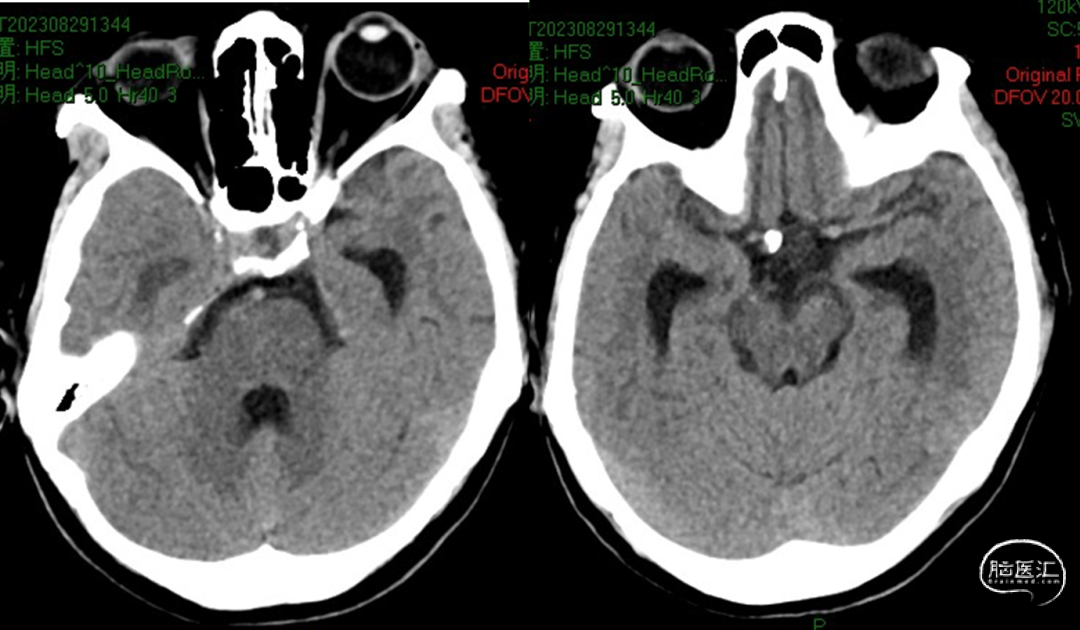

外院CT

2023-08-29

我院CT

2.SAH (H-H II);